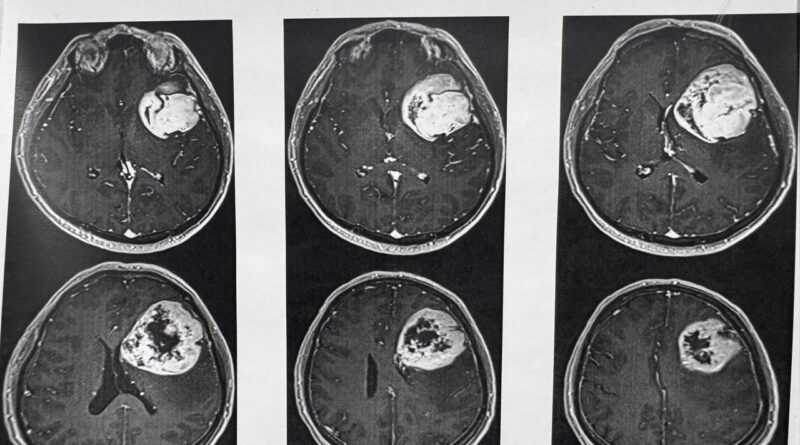

Para Determinar La Realización De Este Procedimiento Y Conocer El Orígen De Los Síntomas, Explicó, El Equipo Médico Del Instituto Le Realizó Al Derechohabiente Estudios De Tomografía Y Resonancia Magnética.

“Se Realizó Tomografía De Cráneo Y, Ante Los Hallazgos, Se Le Practicó Una Resonancia Magnética; Posteriormente, Se Le Detectó Un Tumor De Características Malignas En La Región Frontal Premotora Izquierda”, Detalló.